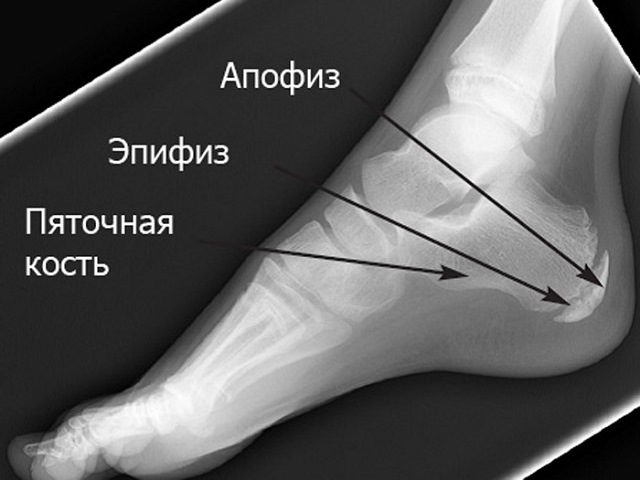

В различных источниках данное заболевание может встречаться под разными названиями: болезнь Шинца, Хаглунда-Шинца (не путать с деформацией Хаглунда), апофизит или эпифизит пяточной кости, остеохондропатия пяточного бугра, а также «болезнь Севера». Обычно оно затрагивает детей, особенно девочек в возрасте 10-14 лет, реже — мальчиков 12-16 лет. Известны случаи, когда заболевание поражало детей даже восьми лет.

Патогенез заболевания можно описать следующим образом:

• После рождения пяточная кость состоит из хрящевой ткани. Для начала ходьбы необходимо окостенение пяток. Этот процесс начинается с «точек окостенения»: первая активируется в 5-6 месяцев, а вторая — в 7-8 лет. В течение этого времени между ними сохраняется хрящевая прослойка, которая исчезает только к 16-18 годам.

• Под воздействием факторов, которые до конца не выяснены (наследственность, нехватка солнечного света, витаминов и минералов, гормональные изменения, проблемы с кровообращением, слишком ранние и интенсивные физические нагрузки), на поверхности пяточного бугра может возникнуть участок асептического некроза.

• Этот участок может провалиться внутрь, что приводит к вдавленному перелому. Кость разделяется на фрагменты, некротизированные ткани постепенно рассасываются, а на их месте формируется новая, здоровая кость.

Таким образом, прогноз заболевания в целом благоприятный. Однако в острой стадии пяточный апофизит или эпифизит может вызывать у ребенка значительные страдания: боль в пятке появляется уже через несколько минут после вставания на ноги, но в покое и ночью неприятные ощущения, как правило, отсутствуют.

Эпифиз — это округлая расширенная конечная часть кости, а апофиз — отросток, который образуется вблизи эпифиза из отдельного ядра окостенения и служит местом прикрепления мышц и связок.

При болезни Хаглунда-Шинца пятка может отекать, при пальпации возникает боль, кожа вокруг становится гиперчувствительной. Иногда наблюдается легкая атрофия мышц голени, а сгибание и разгибание стопы затруднены, в результате чего ребенок начинает ходить «на цыпочках». Лечение обычно консервативное и включает покой, при необходимости иммобилизацию ноги с помощью лангеты, ношение ортопедической обуви или специальных стелек, физиотерапевтические процедуры, витаминотерапию, а в случае сильной боли — прием нестероидных противовоспалительных средств.